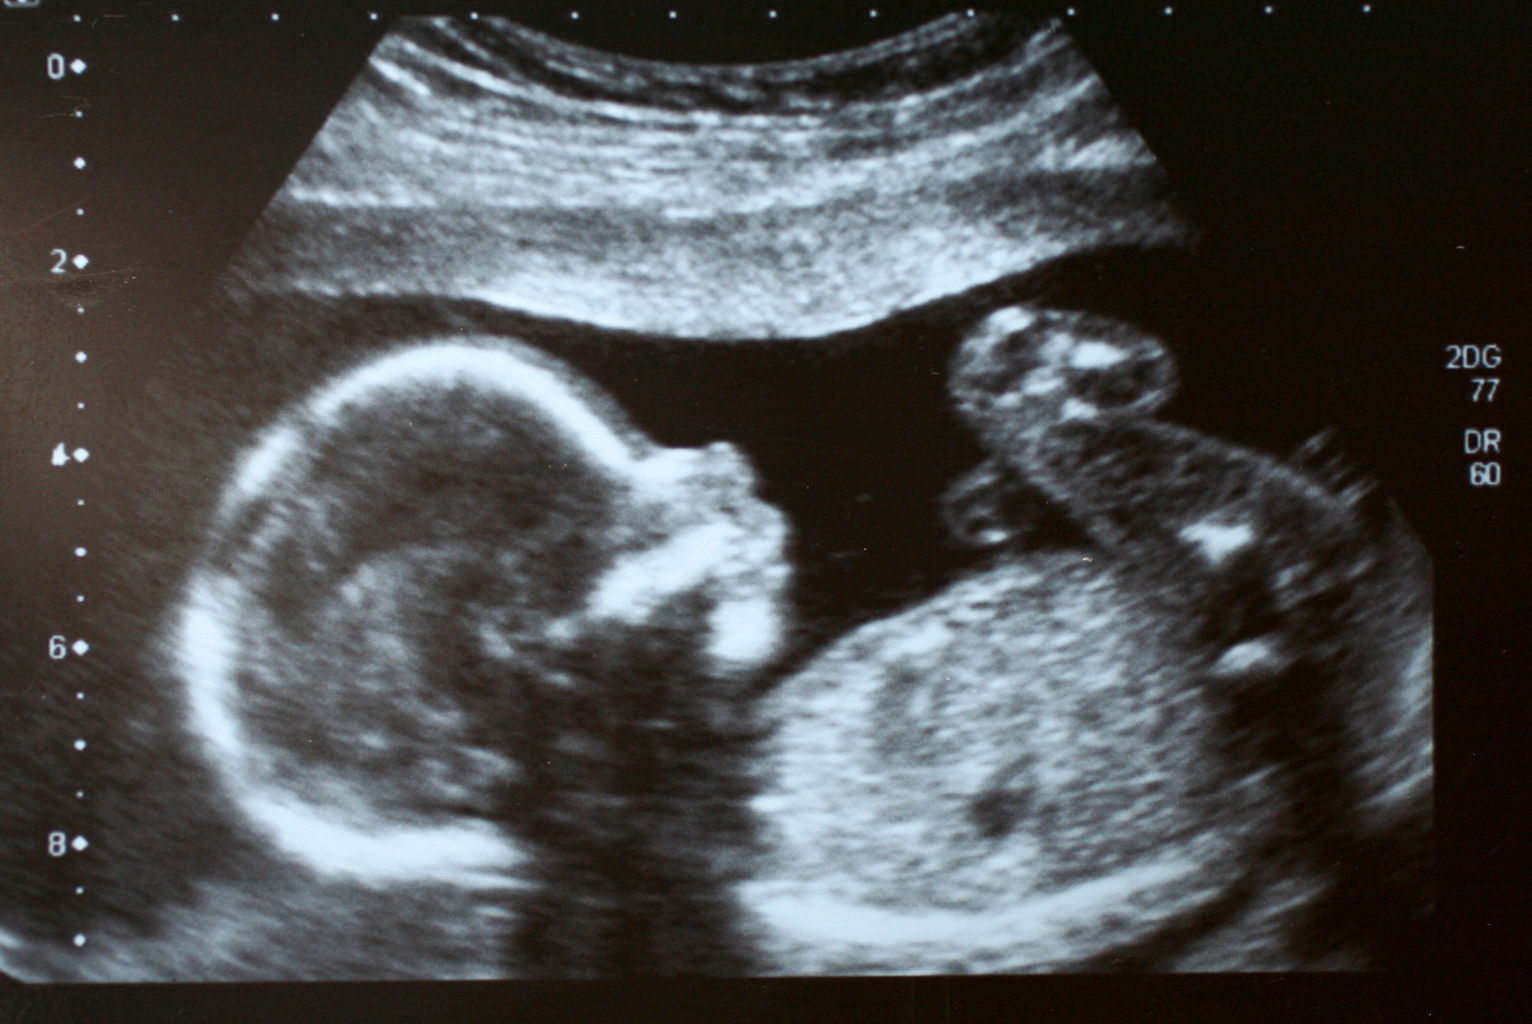

Il Monitoraggio Moderno della Gravidanza

Ai nostri giorni la possibilità di monitorare la fisiologia della gravidanza con indagini ed esami diagnostici ecografici consente alla madre e alla coppia di seguire direttamente lo sviluppo della vita intrauterina del loro bambino e di sentirsene intensamente partecipi.

L'Impatto dell'Ecografia

- Vedere il proprio bambino è un momento importante per lo sviluppo delle capacità genitoriali

- Ancora più significativo per la coppia è il vederlo assieme

- Vedere che il proprio bambino cresce normalmente rassicura i genitori